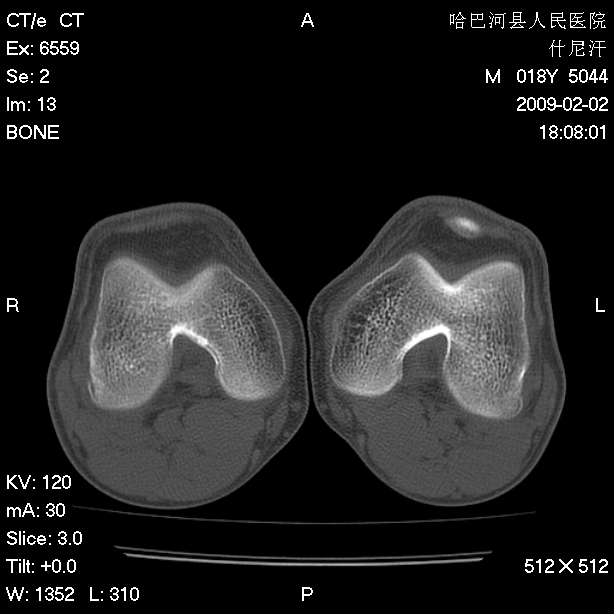

标题: CT17889:外伤后右膝关节反复疼痛3年余 [打印本页]

标题: CT17889:外伤后右膝关节反复疼痛3年余

mri检查,看看半月板情况如何。

可能韧带有问题!

ct未见明显异常。关节腔未见明显积液,半月板未见明显撕裂。但最好还是mri看看韧带及半月板情况。